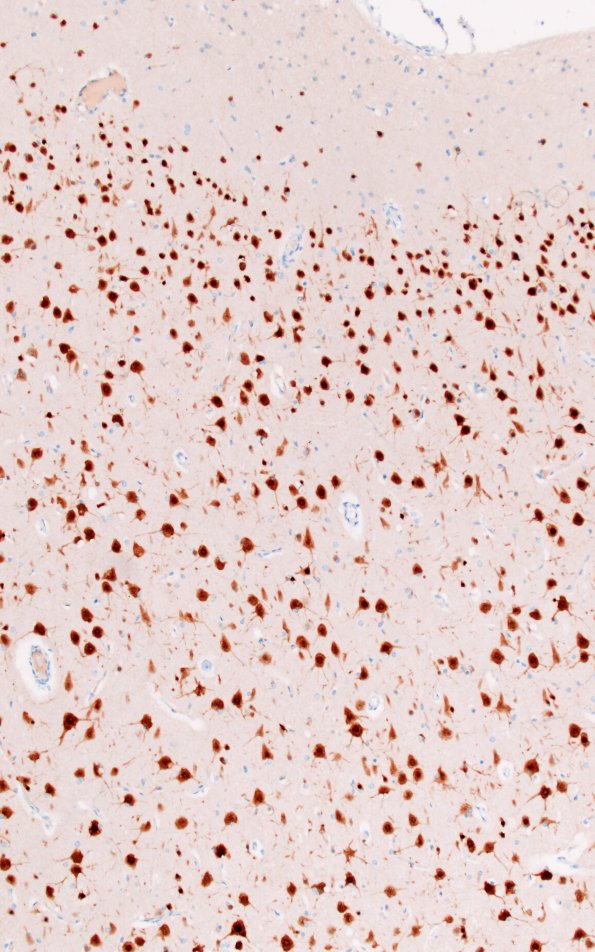

Washington University Experience | DEVELOPMENTAL MALFORMATIONS | Tuberous Sclerosis | 16E2 Tuber (Case 16) WM NeuN 10X 1

The cortical neurons are strongly NeuN immunoreactive stained both in a subpopulation of dysmorphic forms and more normal appearing neurons. (NeuN IHC)